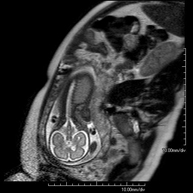

- RM Fetal

Prueba diagnóstica no invasiva que consiste en la obtención de imágenes de alta definición anatómica del feto en la mujer gestante mediante el empleo de un campo electromagnético y ondas de radio (con un emisor y un receptor). No utiliza radiación ionizante. Se puede realizar a partir de la semana 12 de gestación, siendo segura tanto para el feto como para la madre. Se utiliza en el caso de sospechar alguna anomalía congénita morfológica.